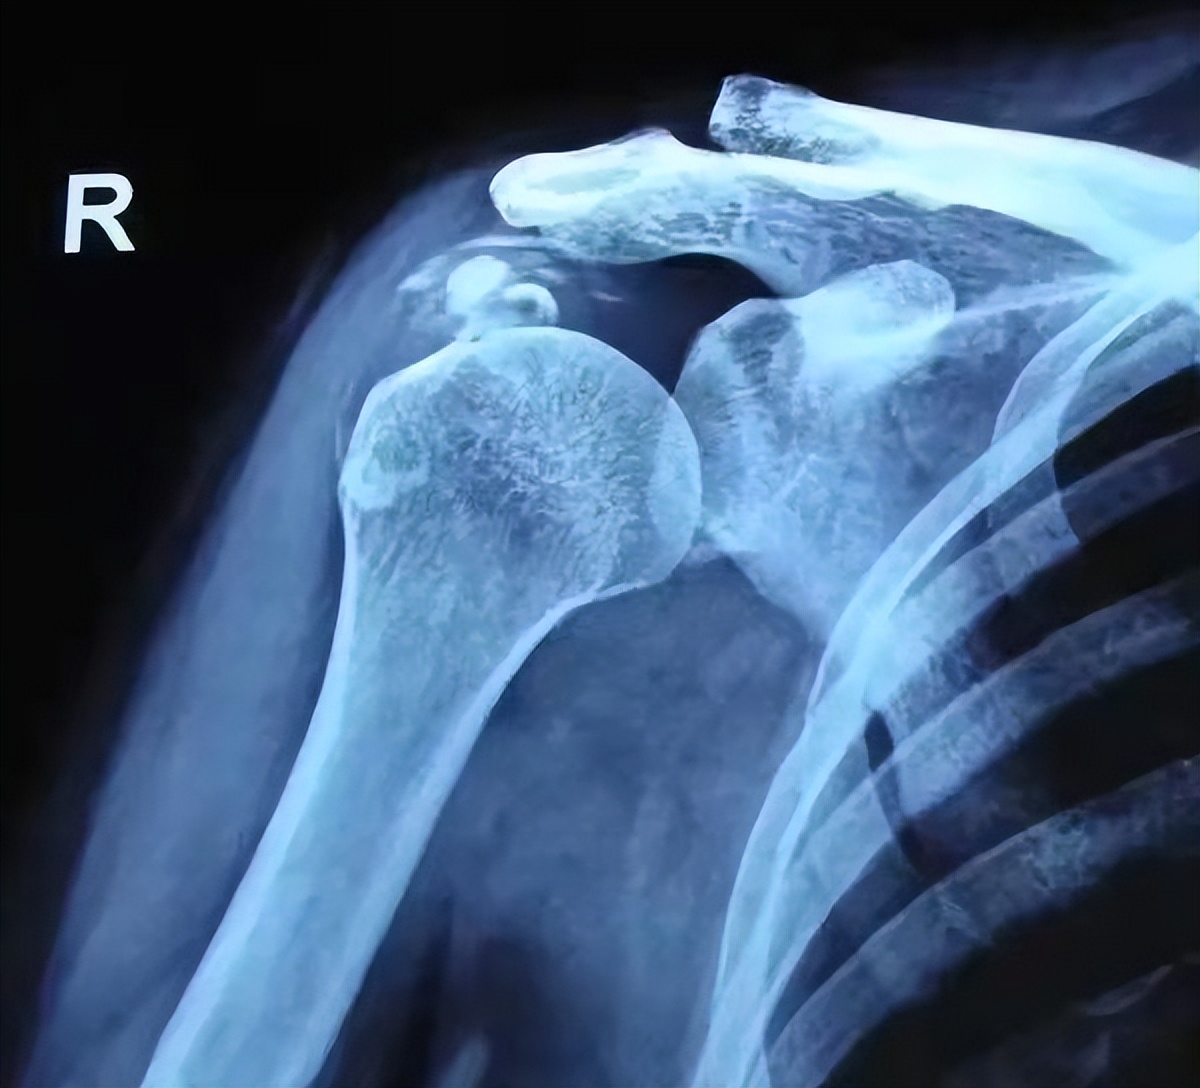

影像学:X线无异常,后期可见肌腱钙化影,MRI可见高信号水肿或肌腱信号减低影

X线表现